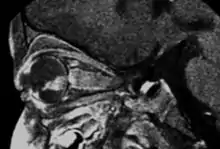

Sagital MRI

- MRI: assessment of local extension to optic nerve, anterior chamber, and orbital fat. Slightly hyperintense on T1, hypointense on T2. Also to rule out trilateral retinoblastoma